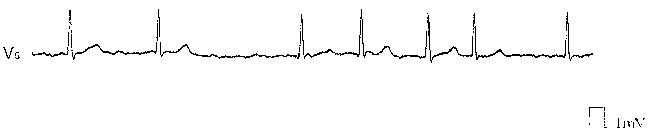

58歳の男性。高血圧で通院中,自覚症状はなかったが不整脈が発見された。身長 163cm,体重 70kg。体温 36.5℃。脈拍 84/分,不整。血圧 142/90mmHg。眼瞼結膜に貧血を認めない。頚部は視診と触診とに異常を認めない。心尖拍動は左鎖骨中線上第5肋間に認める。胸部聴診では心拍の不整を認めるが,呼吸音に異常は認めない。心電図を別に示す。

この患者に必要な検査はどれか。

正解 b

診断 心房細動を伴う甲状腺機能亢進症